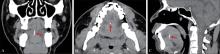

舌内异物在临床上较为罕见,其精确定位和适宜的手术路径选择对于降低手术风险和减少术后并发症至关重要。本文报道1例在影像学精确定位辅助下经舌腹入路取出舌根鱼刺异物的病例。

Foreign bodies in the tongue are rare in clinical practice. Accurate localization and appropriate surgical path selection are essential to reduce surgical risk and postoperative complications. This paper reports a case in which the fishbone foreign body at the base of tongue was removed using a translingual ventral approach aided with imaging localization.